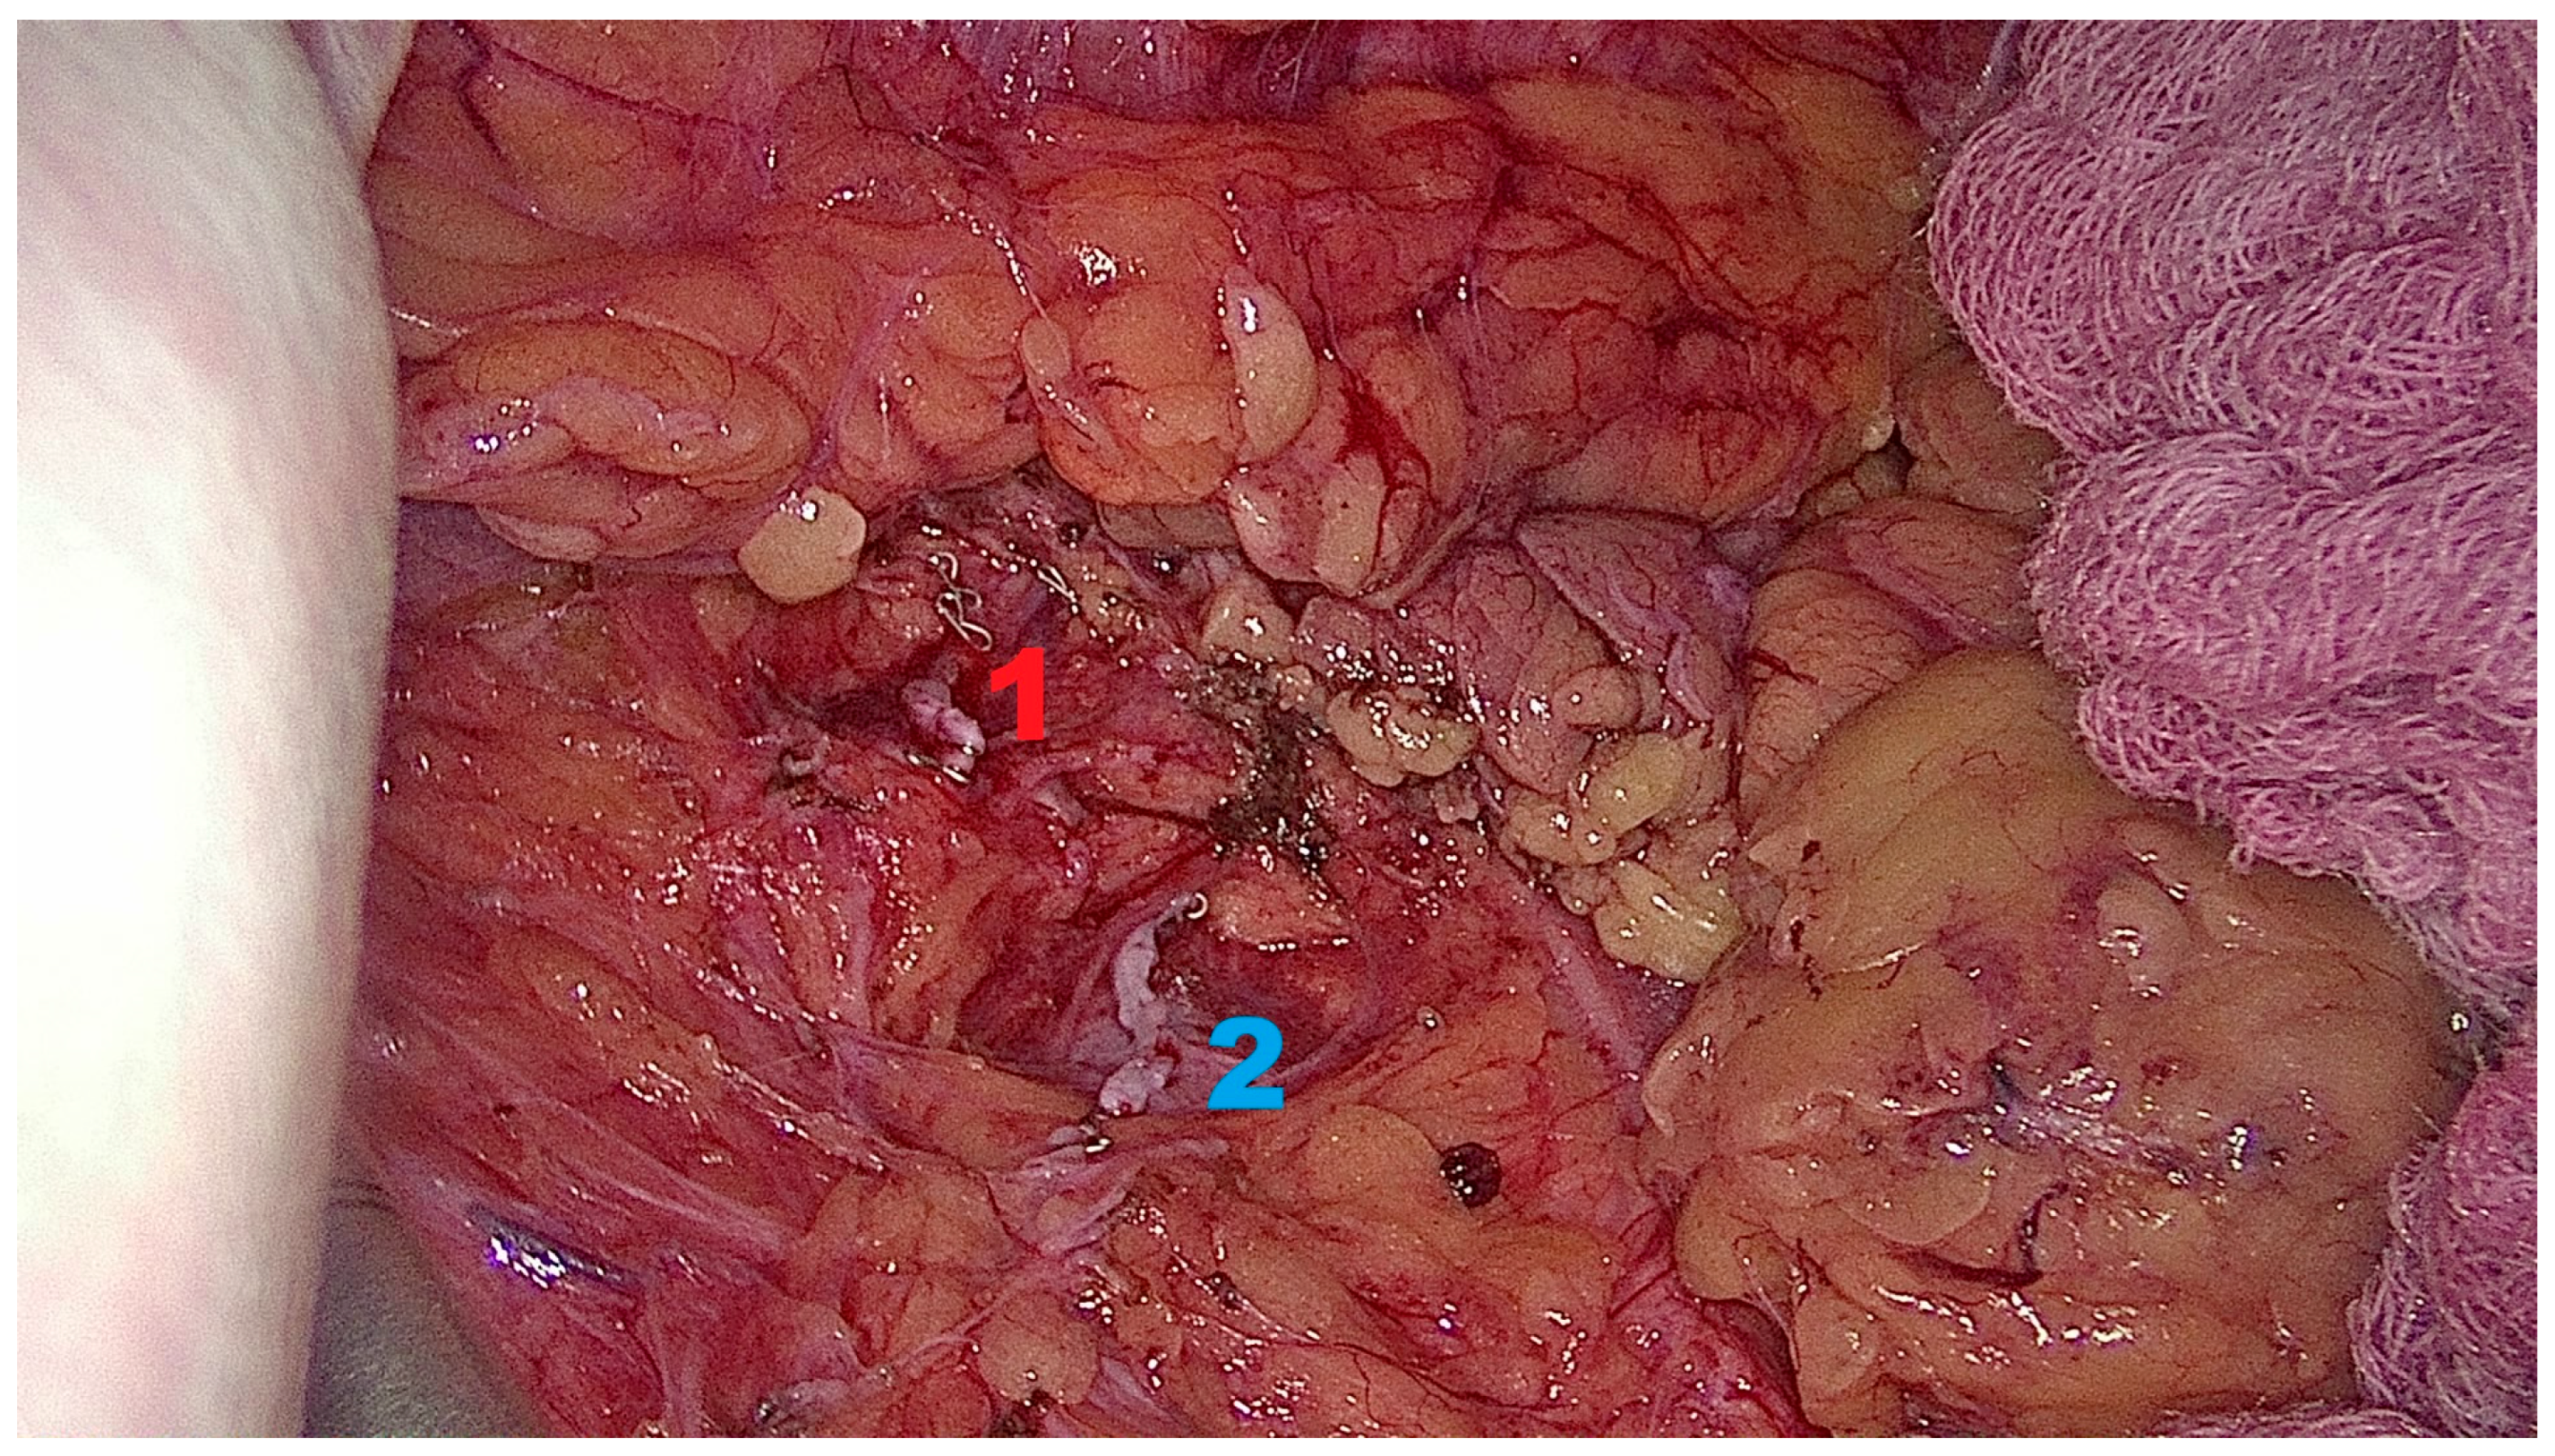

2.6.3. Kidney Mobilization and Hilar Dissection

2.6.4. Graft Procurement and Extraction